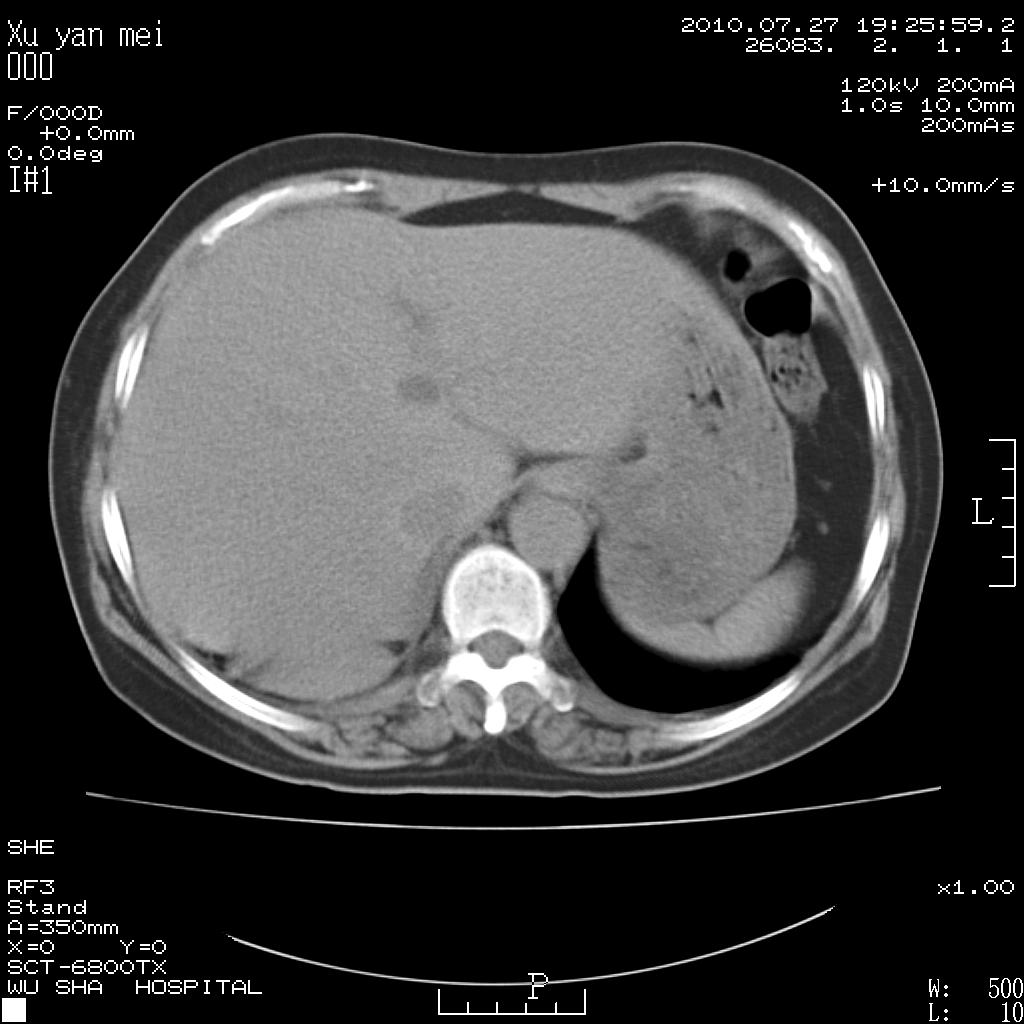

女,60岁,胸痛就诊,右肺结核?炎症?其它?(胸片右侧中上肺野确实看不到什么啊)

1)考虑两肺感染性病变;建议抗炎治疗后复查。2)双侧少量胸腔积液。

1)考虑两肺感染性病变;建议抗炎治疗后复查。2)右侧少量胸腔积液。

右侧少量胸腔积液,段性肺炎。

双肺炎症可能性大,建议抗炎后复查。右侧胸腔少量积液。双侧胸膜轻度增厚。

考虑两肺感染性病变;不除外肺栓;建议抗炎治疗后复查。